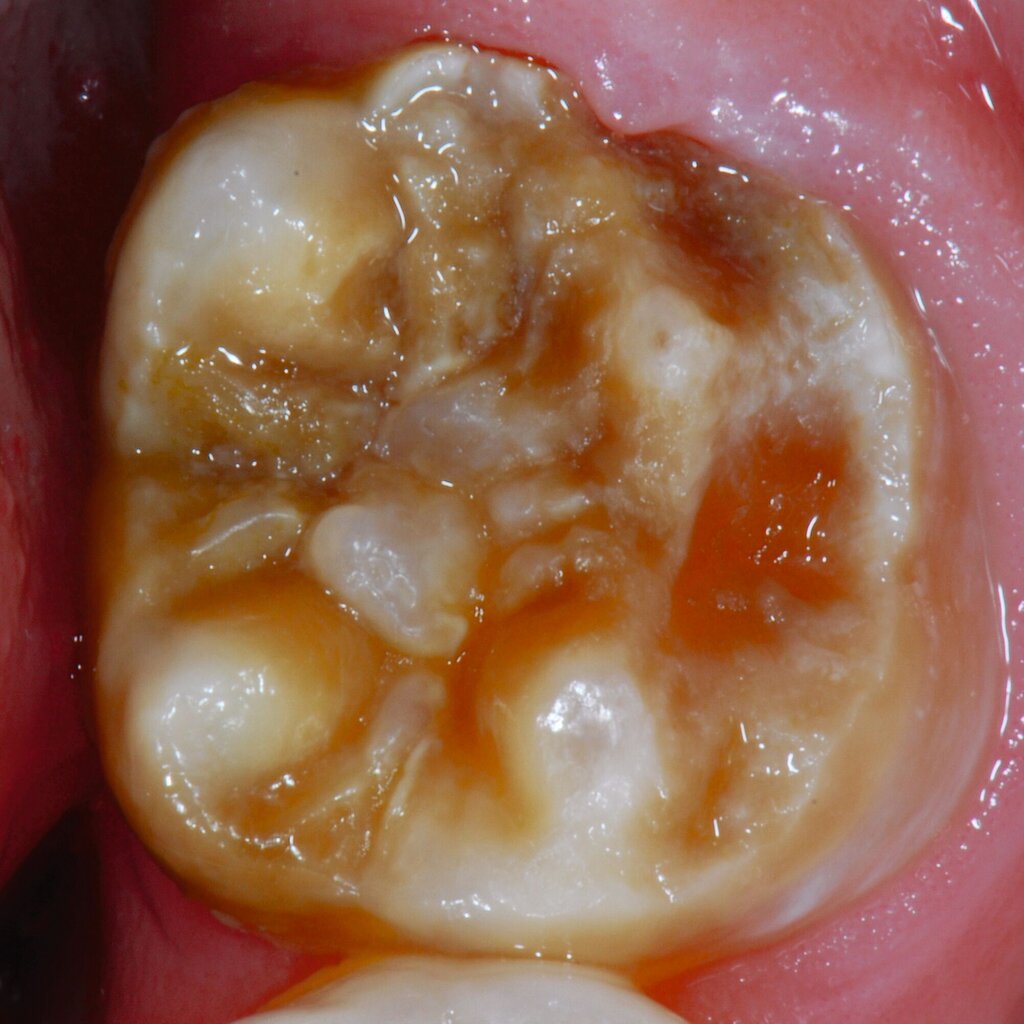

An umfangreich hypomineralisierten Zähnen können Schmelzeinbrüche (engl.: „enamel breakdown“ oder „enamel desintegration“, Abbildung 5) auftreten [Lygidakis et al., 2010; 2022]. Da diese oftmals die Folge einer fehlenden Belastungsfähigkeit des Zahnschmelzes sind und erst nach der Einstellung der Zähne in die Okklusion auftreten, werden sie auch als posteruptive Schmelzeinbrüche bezeichnet. Sie sind häufig im Bereich der Kauflächen beziehungsweise Höcker der Molaren zu finden, führen zur Dentinexposition und damit einhergehend zu ausgeprägten Hypersensitiven insbesondere bei Kindern, deren Zähne gerade erst durchgebrochen sind [Linner et al., 2021].

Für die Dokumentation und Klassifikation der MIH wurden verschiedene Systeme vorgeschlagen. Als historisch und veraltet gilt der (modifizierte) DDE-Index. Demgegenüber haben die Kriterien der EAPD – abgegrenzte Opazitäten (Abbildung 3 und 4), Schmelzeinbrüche (Abbildung 5), atypische Restaurationen (Abbildung 6) – mittlerweile die weiteste Verbreitung gefunden. Diese wurden 2003 erstmals zur Beschreibung der MIH auf empirischer Basis publiziert [Weerheijm et al., 2003] und den Jahren 2010 und 2022 im Rahmen der damaligen MIH-Workshops bestätigt [Lygidakis et al., 2010; 2022].